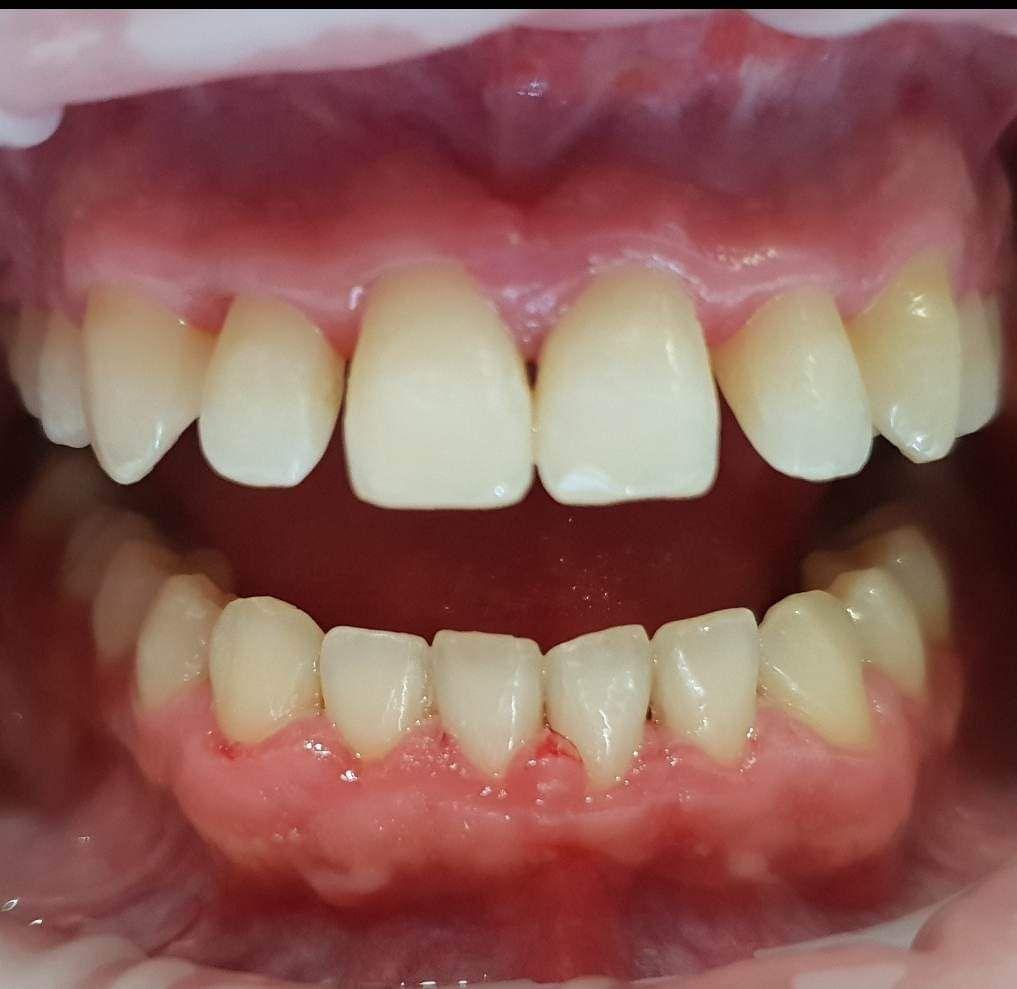

Dzięki precyzyjnej diagnostyce, doktor Magdalena Zawirska opracowała kompleksowy plan leczenia, który obejmował: stomatologię zachowawczą, periodontologię i protetykę stomatologiczną. Zastosowano licówki i korony pełnoceramiczne, przeprowadzając kompleksową rekonstrukcję zwarcia.

Pacjentka może się teraz cieszyć się pięknym i zdrowym uśmiechem